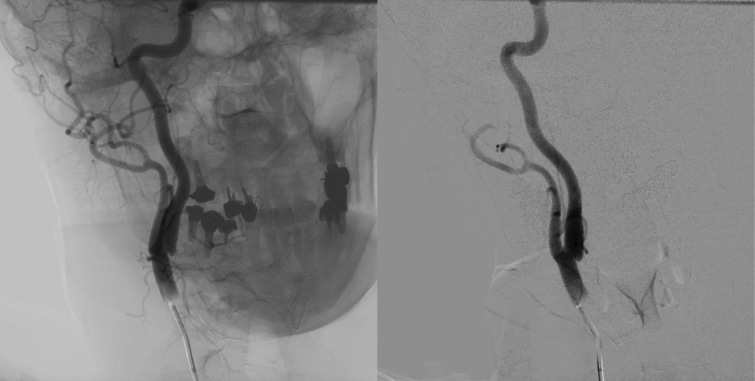

Carotid web is a rare and poorly understood condition associated with cryptogenic and recurrent acute ischemic stroke in young patients without atherosclerotic risk factors. We describe the case of a 58-year-old female patient with hypertension and dyslipidemia who had recurrent ischemic strokes for 5 years. Presence of carotid web was suggested by Doppler ultrasonography and confirmed by digital subtraction angiography. The patient underwent endarterectomy and, due to satisfactory internal carotid reflux, it was decided not to use a temporary vascular shunt. Endarterectomy and arteriorrhaphy with a bovine pericardium patch were performed. Although carotid web can be seen with imaging exams, detection can be challenging and it can mimic other conditions, such as arterial dissection, non-calcified atherosclerotic plaque, and intraluminal thrombus. The ease with which it can go unnoticed or misdiagnosed highlights the need to understand this disease.

Abstract Image